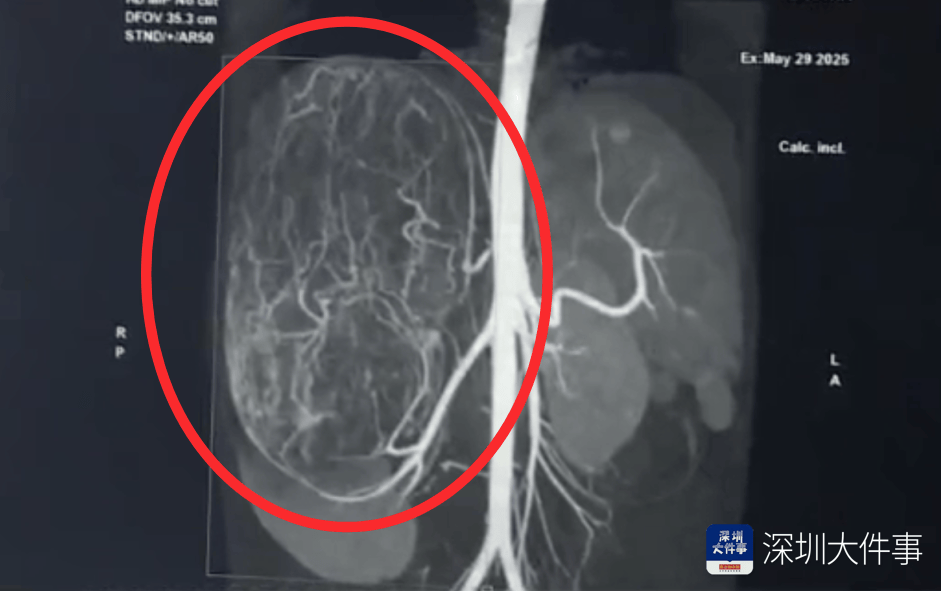

影像检查结果出来时

所有医生都倒吸一口冷气银行虚拟币!

影像检查结果出来,所有人都倒吸一口冷气:一个直径27厘米(比篮球还大)的巨型肿瘤,霸占了整个腹腔右半边银行虚拟币。肝脏被它硬生生挤到了肚脐眼以下的位置!